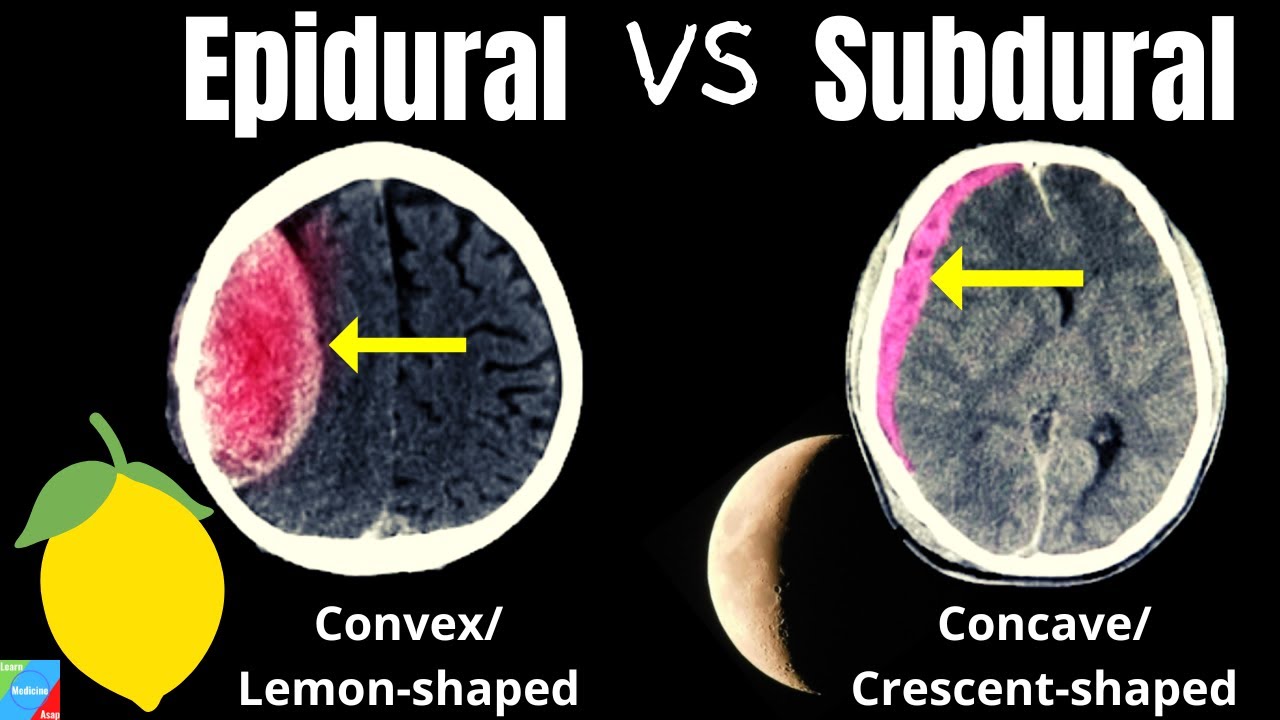

Epidural Hematoma Vs Subdural Hematoma Understanding The Differences It’s important to know the difference between a stroke and a subdural hematoma. both are serious brain issues that can cause big problems. strokes and subdural hematomas are sudden events that affect the brain a lot. what is a stroke? a stroke happens when a blood vessel in the brain gets blocked or bursts. Stroke and subdural hematoma are interconnected and can have devastating effects. understand the link between these two serious medical conditions and how they impact brain health. It’s hard to tell the difference between a subdural hematoma and a stroke. both are serious, but they come from different causes and need different treatments. a subdural hematoma is when blood gathers between the brain and its outer layer. a stroke, or cerebrovascular accident, happens when blood doesn’t reach part of the brain. The only way to differentiate between stroke and chronic subdural hematoma, regardless of symptoms, is with a ct scan of the brain. don’t assume that someone’s symptoms must mean chronic subdural hematoma just because he hit his head recently, either; it can still be a stroke, unrelated to the head trauma.

Download Subdural Hematoma Vs Epidural Hematoma Intracranial It’s hard to tell the difference between a subdural hematoma and a stroke. both are serious, but they come from different causes and need different treatments. a subdural hematoma is when blood gathers between the brain and its outer layer. a stroke, or cerebrovascular accident, happens when blood doesn’t reach part of the brain. The only way to differentiate between stroke and chronic subdural hematoma, regardless of symptoms, is with a ct scan of the brain. don’t assume that someone’s symptoms must mean chronic subdural hematoma just because he hit his head recently, either; it can still be a stroke, unrelated to the head trauma. Subdural hematoma: bleeding between the brain and the dura mater, the outermost membrane covering the brain. now, you might be wondering, “are all brain bleeds considered strokes?” the answer is no. while hemorrhagic strokes are a type of brain bleed, not all brain bleeds meet the criteria for a stroke. A subdural hematoma, on the other hand, is a collection of blood between the brain and its outermost covering (the dura mater), often caused by head trauma. both can lead to neurological. There are several types, each with its own set of challenges: 1. intracerebral hemorrhage: bleeding directly into the brain tissue. 2. subarachnoid hemorrhage: bleeding in the space between the brain and the thin tissues that cover it. 3. subdural hematoma: bleeding between the brain and the dura mater, the brain’s tough outer covering. 4. A subdural haematoma is a serious condition where blood collects between the skull and the surface of the brain, causing pressure on the brain and damaging it. it is a form of bleeding inside the head, specifically in the subdural space, which is the area between the dura mater and the arachnoid mater—two of the three layers of tissue.

Hematoma Epidural Vs Hematoma Subdural Vrogue Co Subdural hematoma: bleeding between the brain and the dura mater, the outermost membrane covering the brain. now, you might be wondering, “are all brain bleeds considered strokes?” the answer is no. while hemorrhagic strokes are a type of brain bleed, not all brain bleeds meet the criteria for a stroke. A subdural hematoma, on the other hand, is a collection of blood between the brain and its outermost covering (the dura mater), often caused by head trauma. both can lead to neurological. There are several types, each with its own set of challenges: 1. intracerebral hemorrhage: bleeding directly into the brain tissue. 2. subarachnoid hemorrhage: bleeding in the space between the brain and the thin tissues that cover it. 3. subdural hematoma: bleeding between the brain and the dura mater, the brain’s tough outer covering. 4. A subdural haematoma is a serious condition where blood collects between the skull and the surface of the brain, causing pressure on the brain and damaging it. it is a form of bleeding inside the head, specifically in the subdural space, which is the area between the dura mater and the arachnoid mater—two of the three layers of tissue.

Differences Between Subdural And Epidural Hematoma Epidural Hematoma There are several types, each with its own set of challenges: 1. intracerebral hemorrhage: bleeding directly into the brain tissue. 2. subarachnoid hemorrhage: bleeding in the space between the brain and the thin tissues that cover it. 3. subdural hematoma: bleeding between the brain and the dura mater, the brain’s tough outer covering. 4. A subdural haematoma is a serious condition where blood collects between the skull and the surface of the brain, causing pressure on the brain and damaging it. it is a form of bleeding inside the head, specifically in the subdural space, which is the area between the dura mater and the arachnoid mater—two of the three layers of tissue.